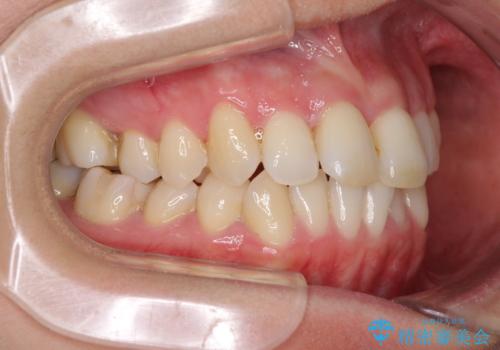

- 奥歯の咬み合わせを気にして来院された患者様です。

上顎骨の幅が下顎骨よりも小さいので、拡大装置により骨幅を広げて上下関係を改善し、その後インビザラインにて歯並びを整えることとしました。

上下の骨幅を改善したことで、スムーズに歯列矯正を行うことができました。

奥歯の咬み合わせを改善する必要があったため、治療は長期化しましたが、きっちりと仕上げることができました。